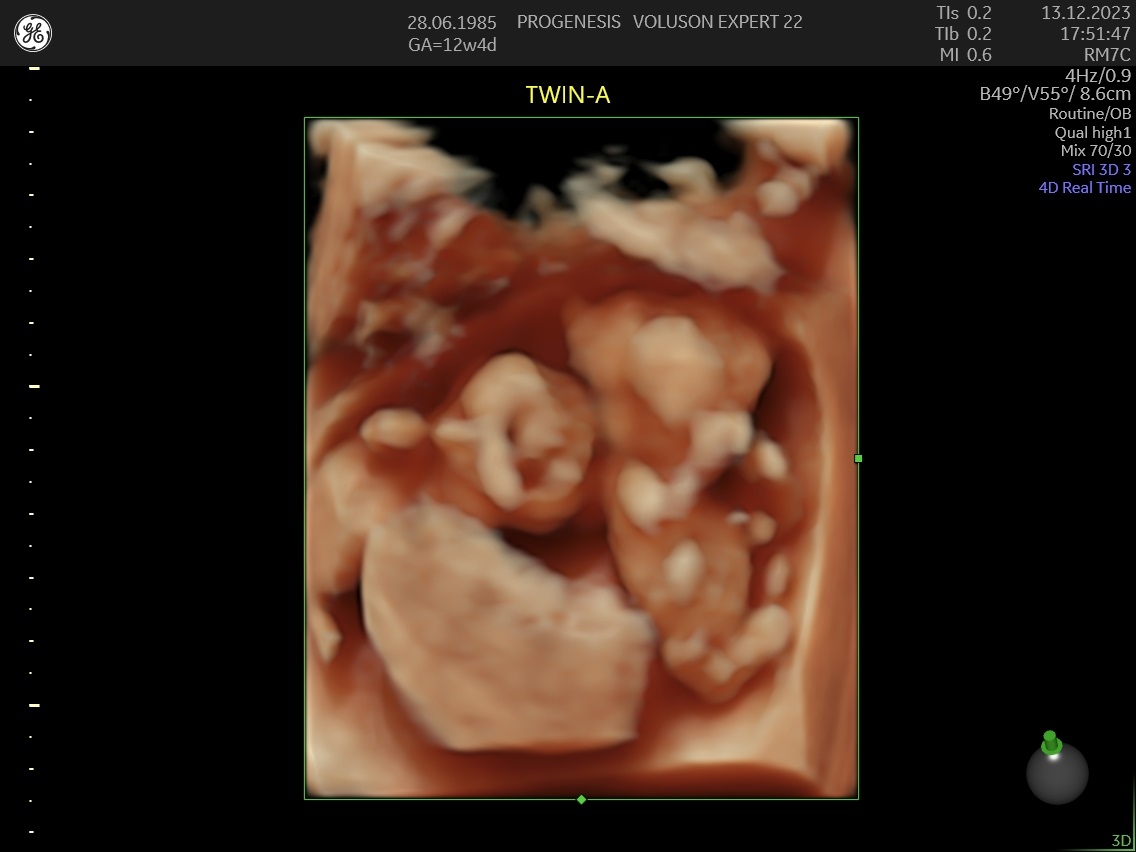

3D/4D LIVE Υπερηχογράφημα

Το 3D/4D LIVE είναι μια νέα τεχνολογία υπερήχων που δημιουργεί εικόνες του εμβρύου σε τρισδιάστατο ή τετραδιάστατο χώρο. Οι εικόνες αυτές είναι πιο ρεαλιστικές από τις παραδοσιακές εικόνες υπερήχων και δίνουν στους γονείς μια πιο ολοκληρωμένη εικόνα του μωρού τους.